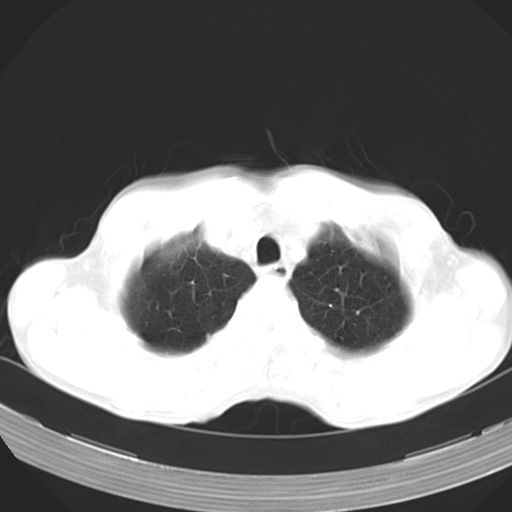

以下是引用苯小孩在2007-5-24 12:47:00的发言:[br]右侧肺门处不均匀密度软组织块影,远端肺组织见斑片模糊影,纵隔内淋巴结明显肿大,边界不清.<纵隔窗第12层面支气管内似见软组织结节>[br]考虑:1、右侧中央性肺癌并阻塞性肺炎并纵隔淋巴结转移可能性大.建议强化或纤支镜进一步检查.[br]2、隆突下淋巴结肿大/食道病变?请做鉴别检查.

以下是引用jw-830在2007-5-24 15:24:00的发言:[br][br] [br] 考虑右肺中央型肺癌并阻塞性炎症,右肺门及纵隔淋巴结转移。 [br] [br][br]